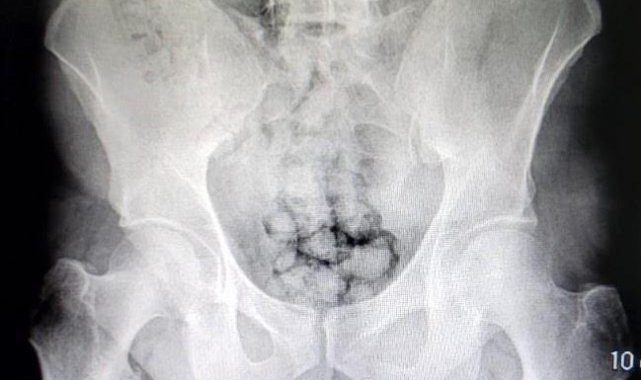

Kayseri İl Emniyet Müdürlüğü Narkotik Suçlarla Mücadele Şube Müdürlüğü ekipleri uyuşturucu madde ticareti yapan iki yabancı uyruklu şahsı takibe aldı. Ekipler, hareketlerinden ve mide bulantılarından şüphelendiği şahısları hastaneye götürdü. Burada röntgen çekinen şahısların midesinde farklı maddeler tespit edildi. Yapılan tıbbi müdahalede şahısların metamfetamin kapsüllerini yutarak midelerinde saklandığı belirlendi. Kayseri Valisi Gökmen Çiçek, operasyonla ilgili olarak, "Ne yaparlarsa yapsınlar Kayseri Emniyetinden kaçamayacaklar. İlimize uyuşturucu sokmak için denedikleri her yol emniyetimizin dikkati sayesinde başarısızlığa uğratılıyor. Bu sefer metamfetamin kapsüllerini midelerinde saklayarak ilimize sokmaya çalıştılar. Emniyetimizin dikkati sayesinde kıskıvrak yakalandılar. Gençlerimizi zehirlemelerine izin vermeyeceğiz. Tebrikler Kayseri Emniyet" ifadelerini kullandı.